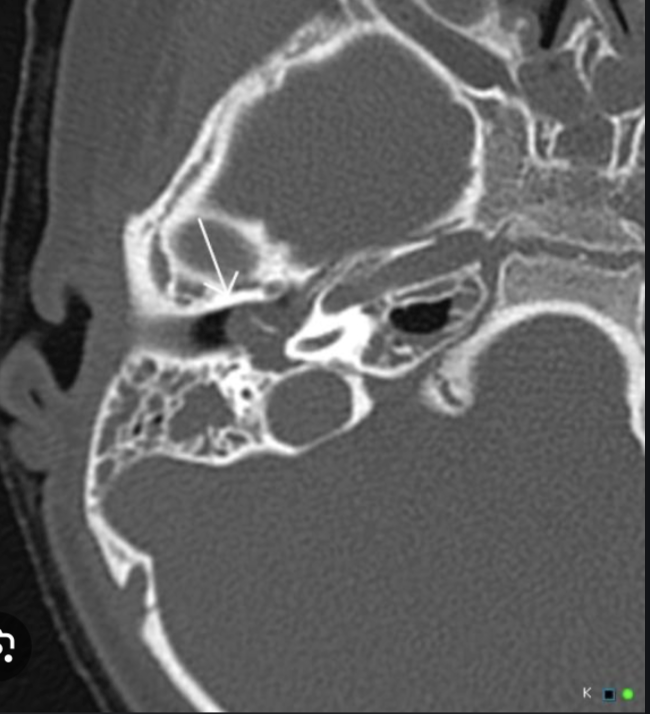

7

A

Otomastoiditis

8